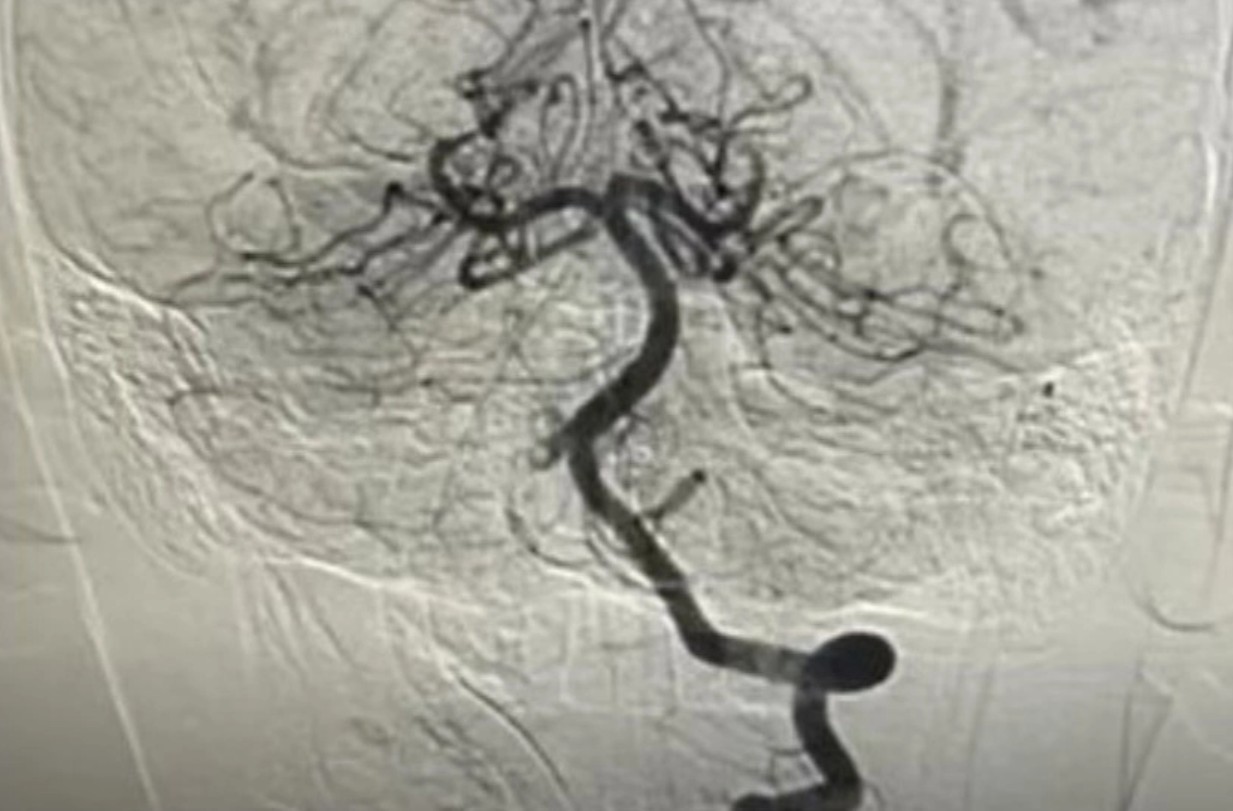

Bác sĩ can thiệp tái thông mạch máu cho bệnh nhi - Ảnh: Bệnh viện cung cấp

Ngay sau hội chẩn liên khoa, bệnh viện đã chỉ định chụp mạch máu não DSA và can thiệp nội mạch cấp cứu. BSCKII Trần Công Bảo Phụng cùng ê-kíp đã tiến hành tiêu sợi huyết tại chỗ kết hợp hút huyết khối, tái thông hoàn toàn mạch máu não cho bệnh nhi.